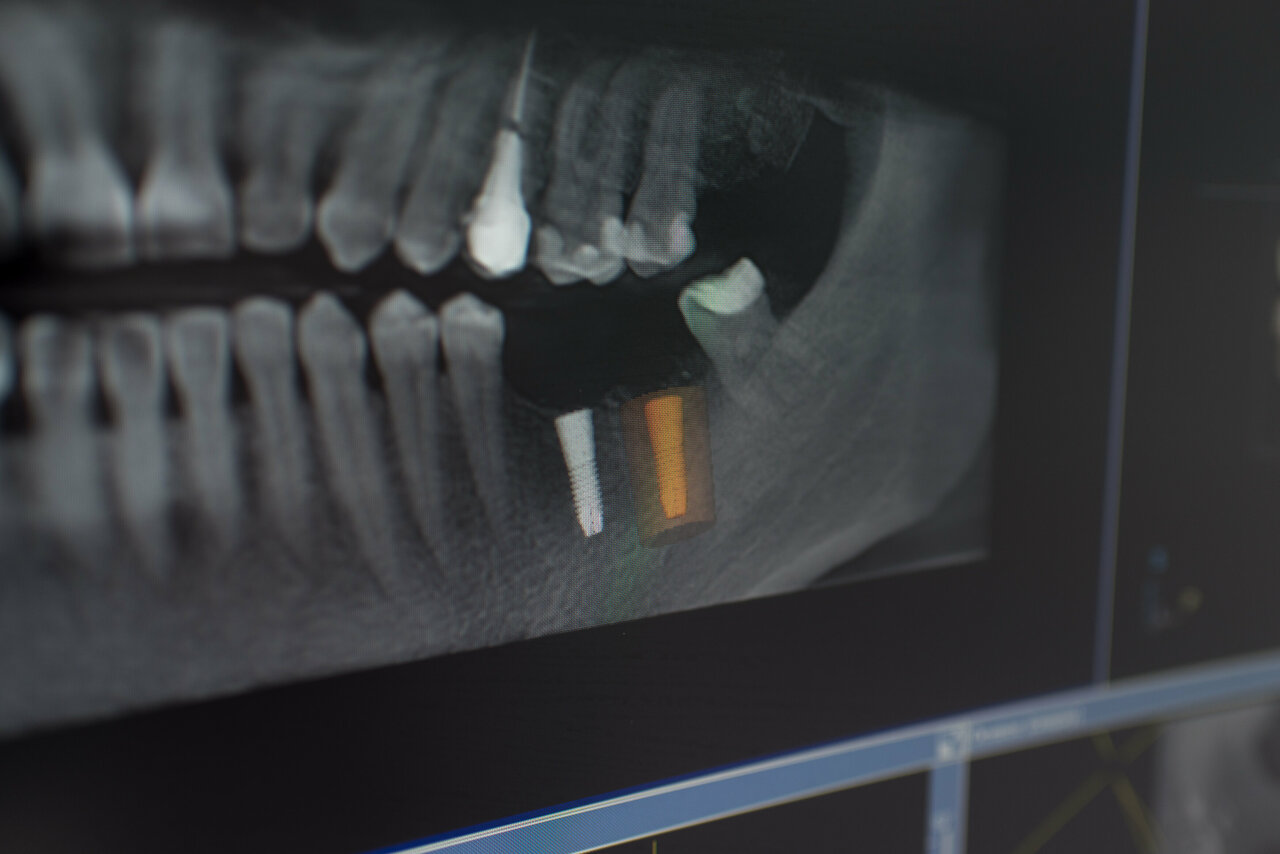

Gold Dent специализируется на различных направлениях стоматологии: общей терапии, хирургии, ортодонтии, эстетической и детской стоматологии, имплантологии, протезировании и эндодонтии. В клинике применяются передовые технологии, такие как цифровая стоматология CAD/CAM, лечение под микроскопом, компьютерная томография и костная пластика.

Если вы на самом деле хотите найти место с достойным сервисом, хорошими врачами, нормальным подходом к клиенту, то вам сюда. На первой консультации мне сразу же предложили сделали 3Д снимок челюсти, и провели консультацию по каждому зубу. У них в кабинете стоит компьютер, на который они мне вывели ЗД снимок моей челюсти, показали все проблемные зубы, объяснили что может случиться, если не вылечить их в самое ближайшее время. Стоимость лечения каждого зуба сказали сразу. Сразу понятно что мне лечат и зачем. Однозначно рекомендую эту клинику.